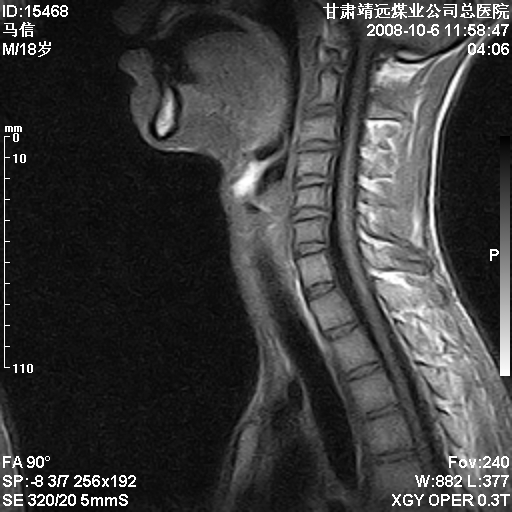

标题: MRI1827:颈椎内异常信号,是不是占位。

患者18岁,学生,在玩耍中受伤来检查,患者喜欢打篮球。颈椎内异常信号影,我们考虑占位,但是不像占位,又考虑硬膜囊的增厚,大家关建看颈椎椎管内的那个异常占位信号

脑脊液流动伪影?

是正常的脑脊液波动伪影

你说的占位是伪影。在我们医院1.5t和3.0t的mr上是经常看见的。